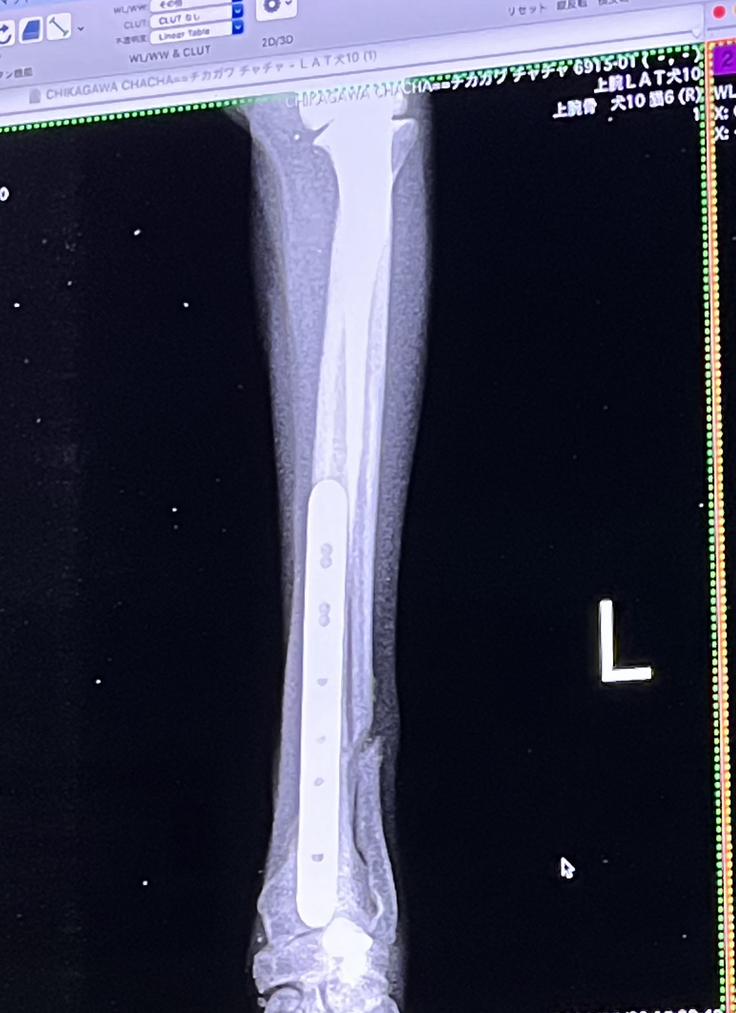

骨折の経過です。まだ細い骨がくっついていないです。みて

病院でレントゲンを撮ったところ、太い骨はだいぶ隙間が埋まってきてるが、細い骨はまだくっついてないと言われました。ですが、細い骨と太い骨の間に骨ができてるとのことです。そこが癒着しないか心配ですが、おそらく大丈夫とのことでした。

細い骨にはプレートは入れておりません。

自然治癒になるそうです。